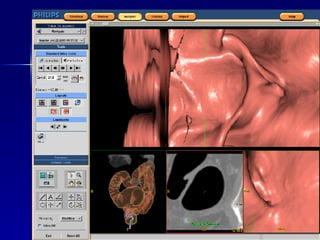

Colonoscopia virtual ABDOMEN